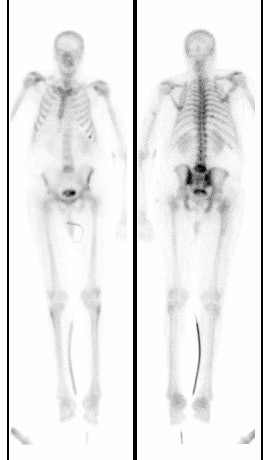

(Case submitted by Dr. Marc Cote, D.O.)The case below illustrates the decreased sensitivity of In-111 WBC imaging for the detection of vertebral osteomyelitis. The whole body bone scan revealed increased tracer activity within L5. The In-111 WBC exam (shown below with Tc-MDP exam for comparison) demonstrated no evidence of increased tracer accumulation in L5 (blue arrow).